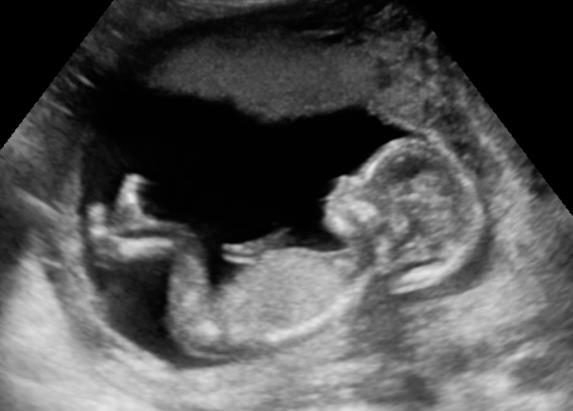

Vitaliteits echo / Termijnecho

De eerste echo wordt gemaakt rond de 10 weken zwangerschapsduur. Hierbij wordt de termijn van de zwangerschap gemeten, dus de uitgerekende datum nauwkeurig vastgesteld. Meestal kan deze echo via de buikwand worden gemaakt, soms wordt het vaginaal gedaan (bij jonge zwangerschappen of als er via de buikwand geen goed beeld wordt verkregen).

Soms is het eerder nodig of gewenst om een echo te maken, zo rond 7-8 wkn. Dat noemen we een vitaliteitsecho. We bespreken samen of dat nodig is.